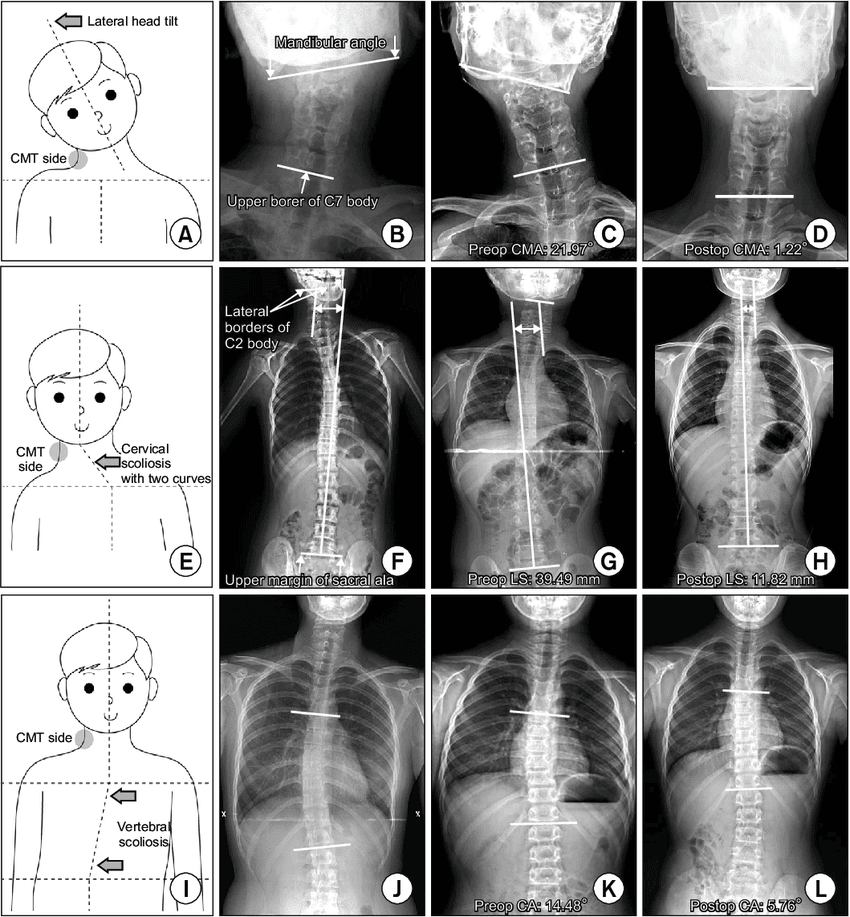

Primeri zamaknjenosti čeljusti/glave in sledenje hrbtenice. Na nobenem rtg posnetku čeljust ni poravnana.